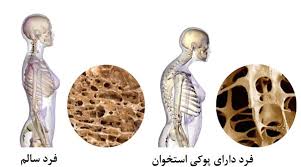

پوکی استخوان چیست؟

یکی از بیماری های متابولیک و شایع بافت استخوان استئوپروز یا بیماری پوکی استخوان می باشد در این بیماری تشکیل بافت استخوانی بسیار کند تر از ساخت آن می باشد بنابراین بافت استخوانی شکننده و ضعیف شده و در نتیجه خطر شکستگی و خرد شدن آن به میزان قابل توجهی افزایش می یابد؛ در نتیجه ممکن است فرد در هنگام سرفه کردن یا زمین خوردن دچار شکستگی های شدید استخوانی شود.

سلولهای بافت استخوانی در معرض فشار و ضربات متعددی قرار دارند لذا باید به طور مداوم سلولها و بافت استخوانی جدید جایگزین بافت استخوانی پیر و فرسوده شود زمانی که فرد در سنین جوانی قرار دارد (زیر 30 سال) سرعت ساخت و ساز بافت استخوان بسیار بالاست اما به تدریج با شروع فرایند پیری سرعت ساخت و ساز بافت استخوانی بسیار کاهش می یابد؛ لذا در این شرایط سرعت تخریب رو به افزایش می گذارد همان طور که پیش تر اطلاع داده شد میزان بروز این بیماری در زنان و افراد مسن بالاتر است. اما سوال اینجاست که علت پوکی استخوان در سنین جوانی چیست ؟ یا علت پوکی استخوان در مردان چه عواملی می تواند باشد ؟ باید بگوییم علل زیادی می تواند سبب پوکی استخوان مردان و همچنین پوکی استخوان زودرس (پوکی استخوان جوانی) می گردد که در ذیل به انها اشاره خواهد شد :